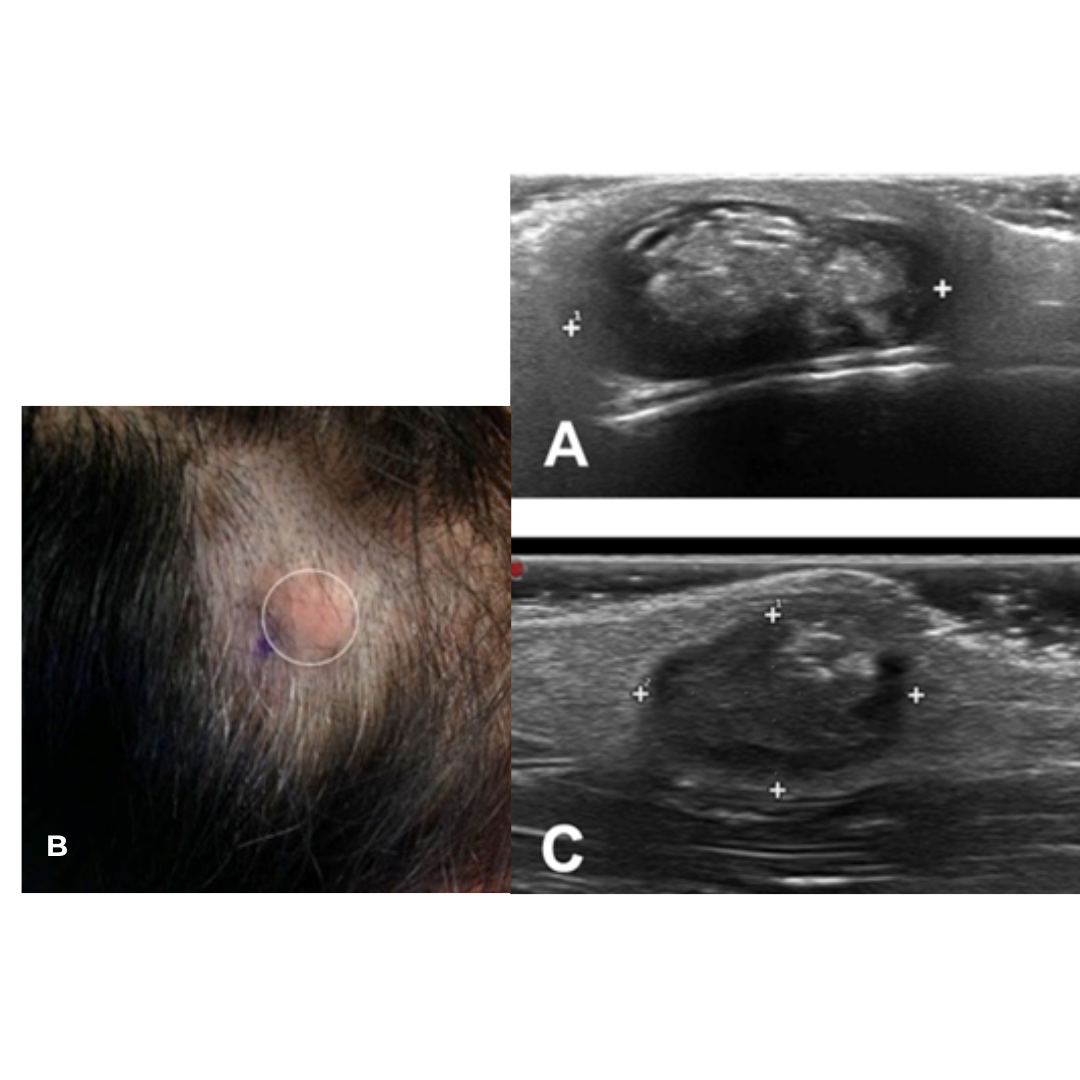

Suelen tener una apariencia heterogénea, en su mayoría hipoecogénica, no vascularizan al Doppler, presentan realce acústico posterior, nódulo liso, no conectado con la epidermis por lo que no presentan punctum, presentan calcificaciones en su interior, que se observarán como líneas hiperecogénicas mejor o peor definidas (imagen 1).

Imagen 1: A y C lesión nodular heterogénea con presencia de calcificaciones, refuerzo acústico posterior ubicada en cuero cabelludo. B) Quiste triquilemal asociado a alopecia